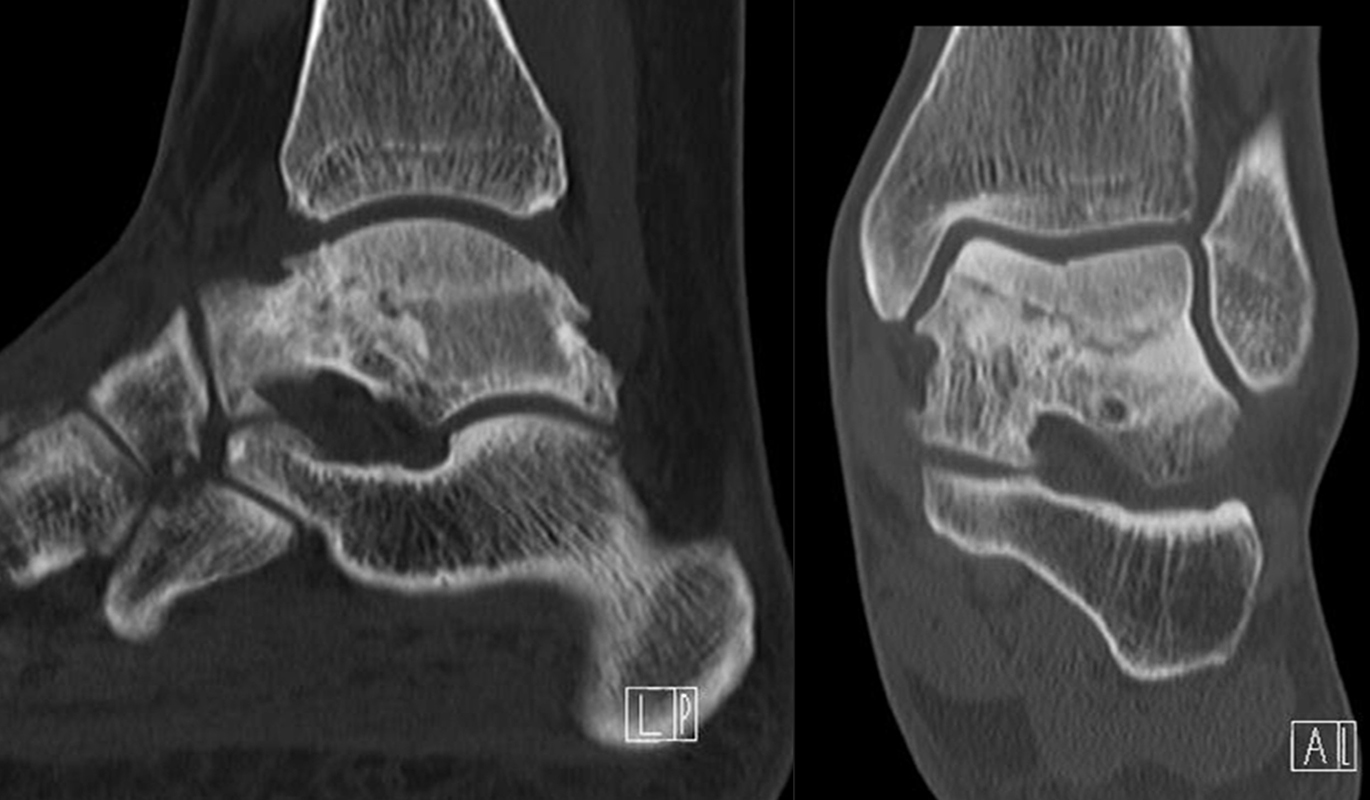

Coalitionen können auf Röntgenbildern wegen überlappender Strukturen häufig nicht sicher diagnostiziert werden, so dass MRT und/oder CT erforderlich sind, um eine Coalitio eindeutig nachzuweisen. Der Vorteil der SPECT/CT liegt darin, dass neben der submilimeter-genauen Darstellung der Anatomie, womit die charakterischten Röntgenzeichen einer Coalitio erkannt werden, auch die Stressreaktion bzw. die Scherkräfte, die auf die Syndesmose oder Synchondrose wirken, sichtbar gemacht werden können. Dabei hat die SPECT/CT eine deutlich höhere Treffsicherheit als die MRT zur exakten Lokalisation der Stressreaktion 44.

Abbildung 4.1.zeigt das Beispiel einer Patientin mit einer Stressreaktion zwischen Processus anterior calcanei und Os naviculare, welche einer fibrösen symptomatischen Coalitio entspricht, die primär in der Bildgebung (Röntgen, MRT) nicht erkannt wurde. Bei Knick-Senk-Fuß erfolgte zunächst eine Talo-Naviculare Arthrodese. Postoperativ nahmen die Schmerzen zu. Anstelle eines SPECT/CT erhielt die Patientin zwei Serien einer Röntgen-Reiz-Bestrahlung. Die Patientin stellte sich in einer auf Fußerkrankungen spezialisierten Klinik vor, die die Patientin zur weiteren Abklärung zu uns überwies. Erst die Abklärung mittels SPECT/CT zeigte die eine fibröse Coalitio zwischen Processus anterior calcanei und Os naviculare bei vollständig reizlos durchbauter Talo-Navicularer Arthodese. Es wurde daraufhin eine erfolgreiche konservative Therapie u. a. mittels gezielten Injektionen und Stosswellen eingeleitet.

Die Abbildungen 4.2.a bis d zeigen den typischen Aspekt einer talacalcanearen Coalitio. Es besteht nur eine linksseitige, symptomatische Coalitio talocalcaneare (4.2.a und c); das 35 Tage zuvor angefertigte MRT zeigt keine auffälligen Signalveränderungen (4.2.b und d).

Abbildung 4.3. zeigt die Ursache für rechtsseitige Sprunggelenksbeschwerden bei einem Patienten mit talocalcanearen Coalitionen: nur die osteochondrale Läsion an der distalen rechten Tibia ist die Ursache des Schmerzes. Die bilateralen talocalcanearen Coalitionen sind asymptomatisch.